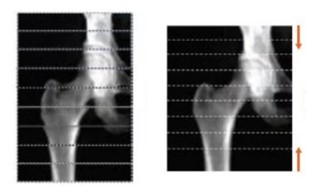

Technical Tips_detector array05.jpg

正確な面積を提供する独自の再構成技術 MVIR

(Multi-View Image Reconstruction)

左:再構成前

右:再構成後

これにより、体軸方向の拡大誤差を最小にし、実際の骨の高さに画像を構築します。この独自の再構成技術 MVIR (Multi-View Image Reconstruction)により、各スイープ間で体軸方向に生じた歪みもなくし、正確な面積の提供が可能となりました。